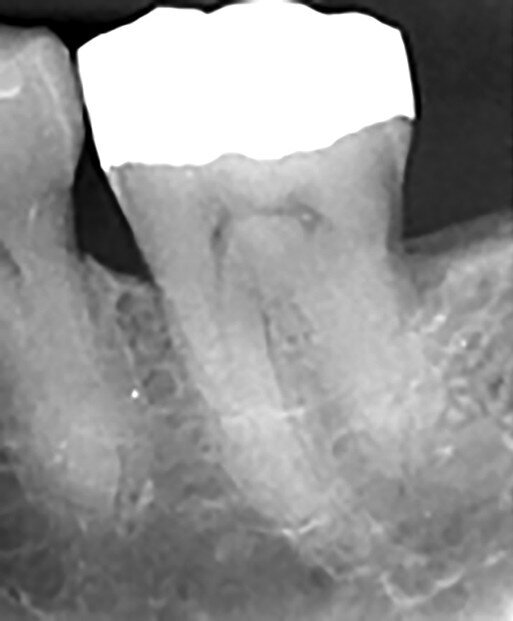

Figs. 4a et b : Cavités d’accès réalisées dans une molaire préparée pour une couronne et requérant un traitement canalaire (à gauche). Radiographie postopératoire (à droite) montrant le résultat admirable de la mise en forme du canal radiculaire, du nettoyage et de l’obturation – malgré la dimension minimale de l’orifice d’accès. À noter le plafond de la cavité pulpaire qui subsiste largement. (Photos : fournies par le Dr Steve Baerg)